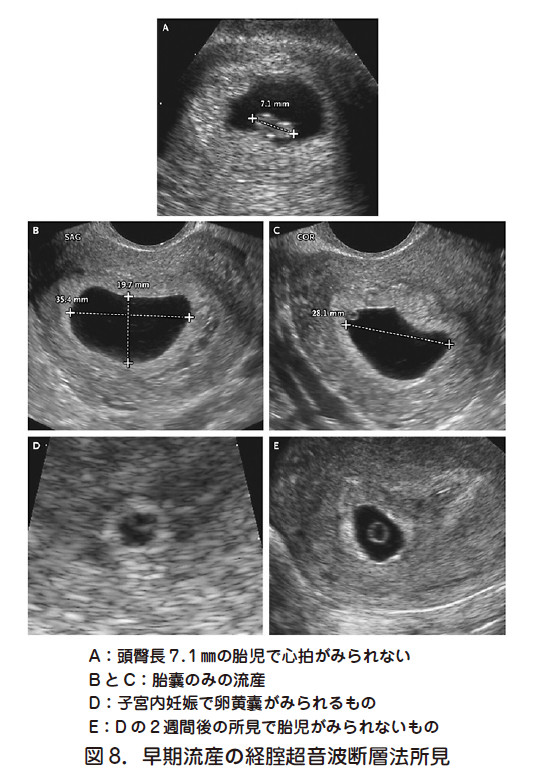

1 早期流産の処置方法の選択 日本産婦人科医会

8 稽留流産の診断 日本産婦人科医会

8 稽留流産の診断 日本産婦人科医会